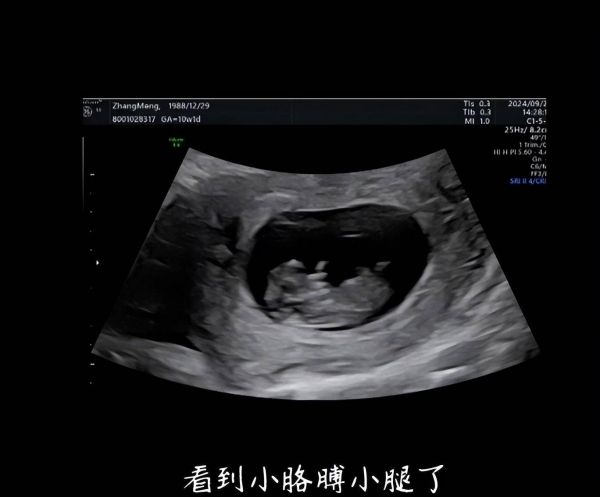

视频中,张檬晒出肚子里宝宝的B超照,称看到小胳膊小腿了。她还感慨相爱第5年终于拥有爱的结晶。